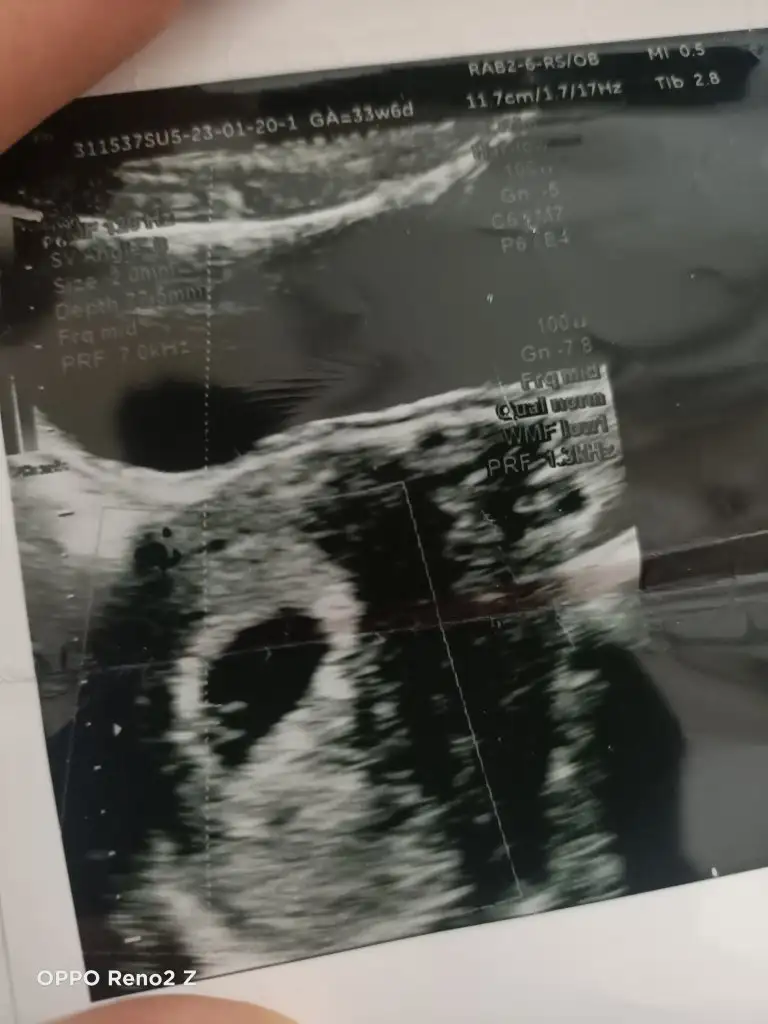

Karından canım ama ikizlik şüphesi var sence ikiz de olabilir mi yoksa birisi yolk kesesimi doktorum net birşey söylemedi🥰❤️

Canım plasentanın parlak tarafı assa doğru duruyor asla anlamadım bebegn konumuna göre plasentanın sola daha yakın oldgnu düşünürsek erkek dye tahmin yuruteblrm canim.

Bu arada ikiz gibi evet gerçekten :)

Cidden ikiz mi dersin ama tek kalp atışı vardı doktor da pek emin olamadı yolk kesesi olabilir dedi bende hayatımda ilk gördüğüm ultrason görüntüsü olduğu için hiç bi bilgim yok günlerdir deliricem yani🫣🥹hormonlarım zaten tavan tek gebelikte böyle olmuyor mu özelden daha netlerini atsam sana bakabilirmisin🙈🥹🥹🥹❤️🙏

Betahcg varsa ordan tahmin yuruteblrm kuzum dur tekrar inceleyeyim Bn ultrason unu